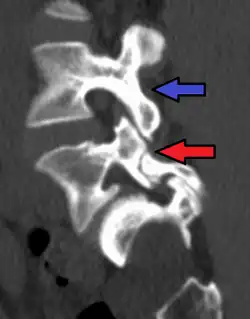

-

Anterolisthesis L5/S1 -

Anterolisthesis L5/S1. Blue arrow normal pars interarticularis. Red arrow is a break in pars interarticularis. -

Anterolisthesis L5/S1